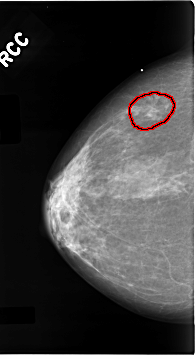

C_0096_1.RIGHT_CC

RIGHT_CC LINES 4656 PIXELS_PER_LINE 2544 BITS_PER_PIXEL 12 RESOLUTION 50 OVERLAY

FILE: C_0096_1.RIGHT_CC.OVERLAY

TOTAL_ABNORMALITIES 1

ABNORMALITY 1

LESION_TYPE CALCIFICATION TYPE PLEOMORPHIC DISTRIBUTION CLUSTERED

LESION_TYPE MASS SHAPE IRREGULAR MARGINS ILL_DEFINED

ASSESSMENT 5

SUBTLETY 4

PATHOLOGY MALIGNANT

TOTAL_OUTLINES 1

BOUNDARY